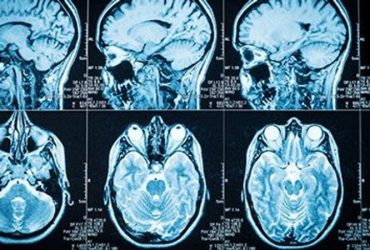

Findings based on neuroimaging and clinical data can speed knowledge of efficacy to one week